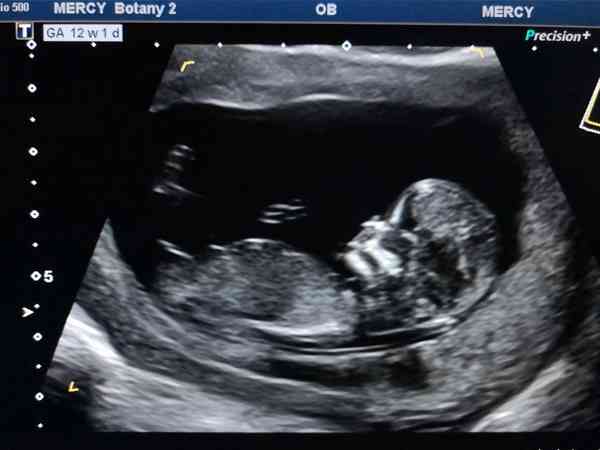

一般情況下,檢查結果顯示胎囊下方有暗區不嚴重。在懷孕早期,孕囊可能尚未完全發育,在進行NT檢查時,可能會出現類似於葡萄狀的結構,這是正常的生理結構。12周+1天nt檢查有4cm暗區暫時不能進行準確判定,需要繼續觀察,過兩到三週之後複查超聲,專門看一下這一塊積液的面積大小變化,如果變大了,就要增加臥床時間。4cm暗區有可能是空的腔隙也可能是出血,因為從來沒有過出血的,是積血的可能性比較小,但也不能完全除外,產婦宮頸和宮腔是有個夾角,宮腔裡面有孩子,宮腔又是倒三角形,確實有可能在宮頸和宮腔交接的部位,孕囊就壓不住、壓不上,所以有空的腔隙。